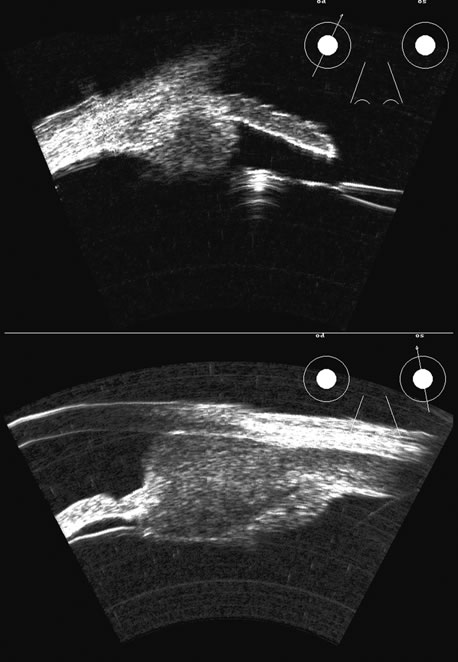

Two-dimensional scans through complex three-dimensional structures, such as preretinal membranes and proliferative membranes, can be confusing unless mapped with three-dimensional conceptualization techniques. Bronson and colleagues15 have emphasized three-dimensional thinking. Although new digital three-dimensional ultrasound systems allow direct volume visualization, it remains useful to understand the technique of conceptualizing three-dimensional structures from individual sections.16 Preretinal membranes (Fig. 15), which may resemble traction detachments in thickness and reflectivity, can often be identified by turning the scan plane of the B-scanner at right angles: the disciform retinal elevation is still seen while the linear nature of a traction sheet is revealed.17 A three-dimensional rendering of a retinal detachment can directly show the conformation of three-dimensional structures (Fig. 16), and images of individual planes can be perceived.

Fig. 15. A preretinal membrane is attached to the retina, producing a traction retinal detachment. A single-scan plane is often confusing: serial scans and movement of the patient's eye (kinetic scan) are required to conceptualize the vitreoretinal anatomic relationships. Computer reconstruction provides a significant advance in this area for ease of interpretation.

Fig. 16. 3D depiction of a retinal detachment can be helpful in situations in which there is ambiguity among retina, choroid, and schisis. The 3D rotatable display can be perceived from different perspectives, often aiding in the certainty of diagnosis.